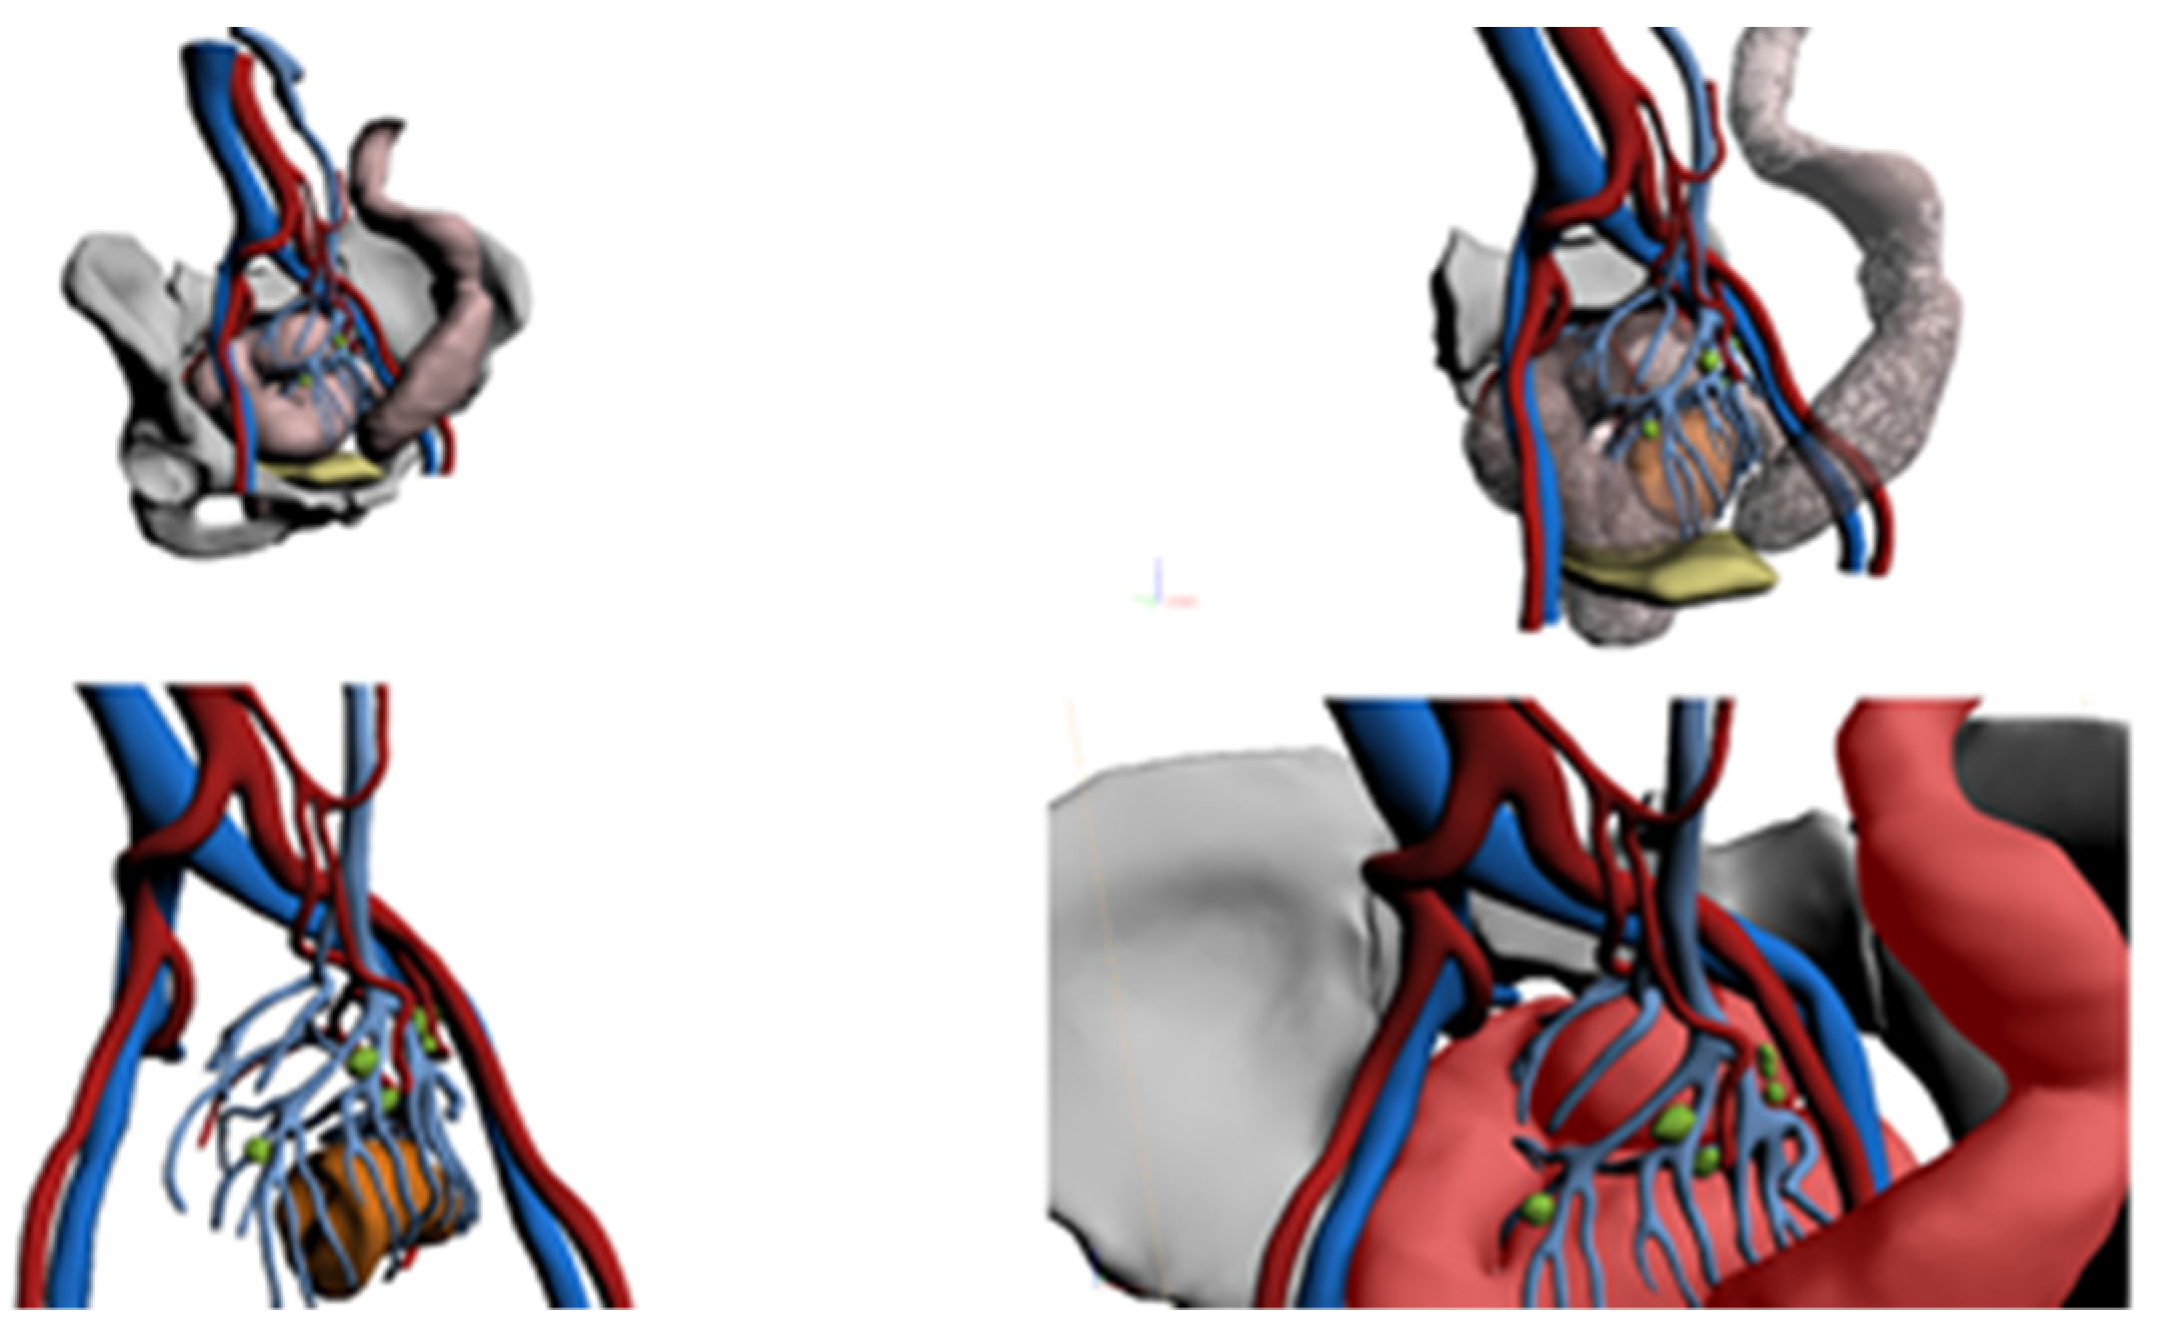

4. Case Descriptions

4.4. Case 4

4.5. Case 5